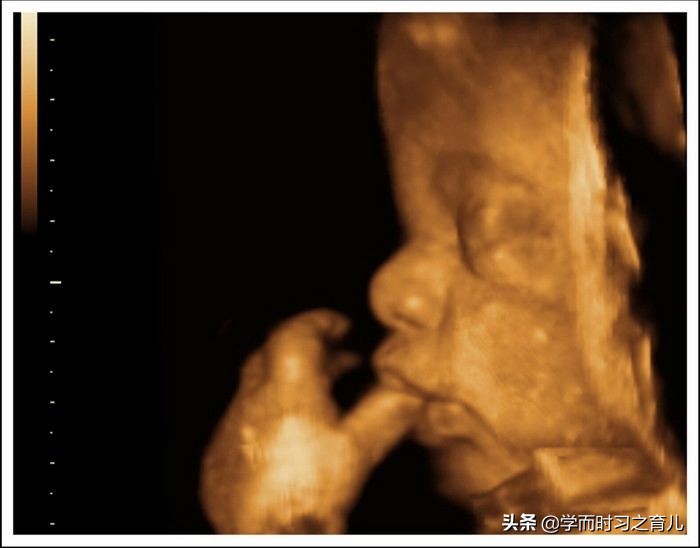

2、胎儿总是挡住脸

其实四维彩超对胎儿面部的检查内容还是比较多的,比如嘴巴、鼻子等等,但如果胎儿总是用手挡住脸,那医生就无法看清其局部发育情况,从而导致产检不顺利。

此外,针对这种现象,准妈妈是最无奈的,因为宝宝挡住脸,不像宝宝动得厉害,准妈妈还可以调整一下,一般宝宝挡住脸,孕妈咪不管做什么,宝宝都不会那么挺好的配合,当然了,有些宝宝比较听话,妈妈一说,宝宝就放下手了。